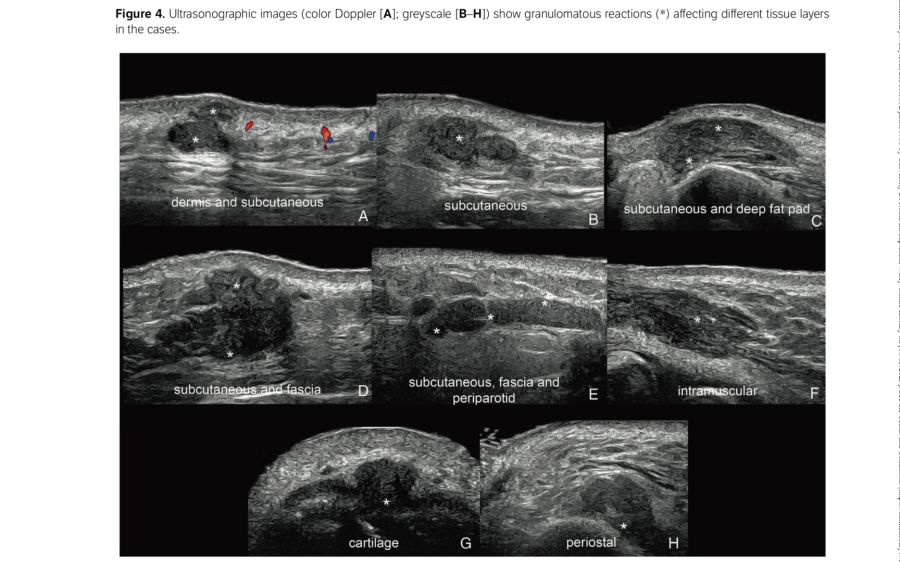

L'incidenza delle complicazioni da filler a base di HA del volto è aumentata significativamente. In questo contesto, l'ecografia, e in particolare l'ecografia Doppler, è diventata uno strumento importante per migliorare la sicurezza dei trattamenti con filler a base di acido ialuronico. L'esame ecografico può aiutare sia nella prevenzione delle complicazioni sia nella loro gestione utilizzando le ialuronidasi in ecoguida. Per avvalorare questo discorso, uno studio molto importante (DELPHI) riguardo l’utilizzo dell’ecografia nelle infiltrazioni del volto, dichiara una forte raccomandazione (obbligo) nell' utilizzo in alcune aree più sensibili ad eventi vascolari.